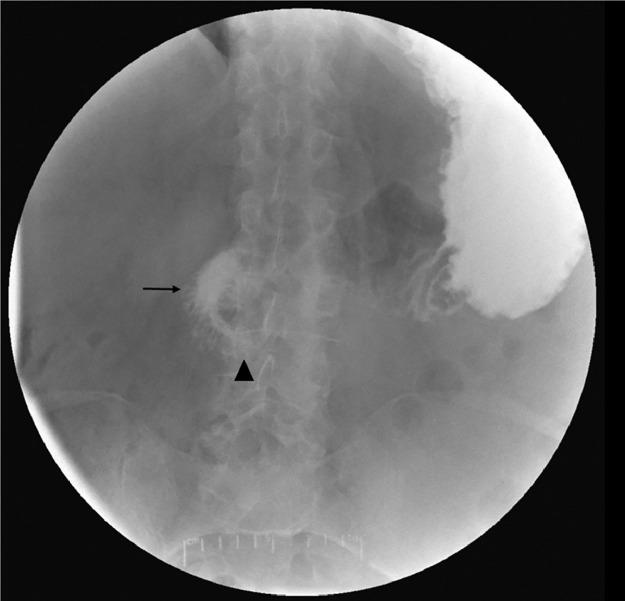

Visceral aneurysms of the pancreaticoduodenal arcades are rare. Although these aneurysms are often asymptomatic and identified incidentally on cross-sectional imaging, aneurysm rupture presents significant morbidity. Ruptured pancreaticoduodenal arcade aneurysms typically present with abdominal pain, hemorrhagic shock, or gastrointestinal bleeding. A 72-year-old male presented with nausea and vomiting and was found to have imaging evidence of duodenal obstruction. This was due to a duodenal intramural hematoma caused by a ruptured submucosal aneurysm supplied by a branch of the inferior pancreaticoduodenal artery in the presence of median arcuate ligament compression of the celiac artery. This was subsequently treated with endovascular embolization with clinical improvement in duodenal obstruction. This case illustrates an unusual presentation of a ruptured pancreaticoduodenal arcade aneurysm.

胰十二指肠动脉弓内脏动脉瘤较为罕见。尽管这些动脉瘤通常无症状,在横断面成像检查时偶然发现,但动脉瘤破裂会导致严重的发病情况。破裂的胰十二指肠动脉弓动脉瘤通常表现为腹痛、失血性休克或胃肠道出血。一名72岁男性因恶心和呕吐就诊,影像学检查发现有十二指肠梗阻的证据。这是由于胰十二指肠下动脉分支供应的黏膜下动脉瘤破裂导致十二指肠壁内血肿,同时存在腹腔干正中弓状韧带压迫。随后对其进行了血管内栓塞治疗,十二指肠梗阻的临床症状有所改善。该病例说明了破裂的胰十二指肠动脉弓动脉瘤的一种不寻常表现。